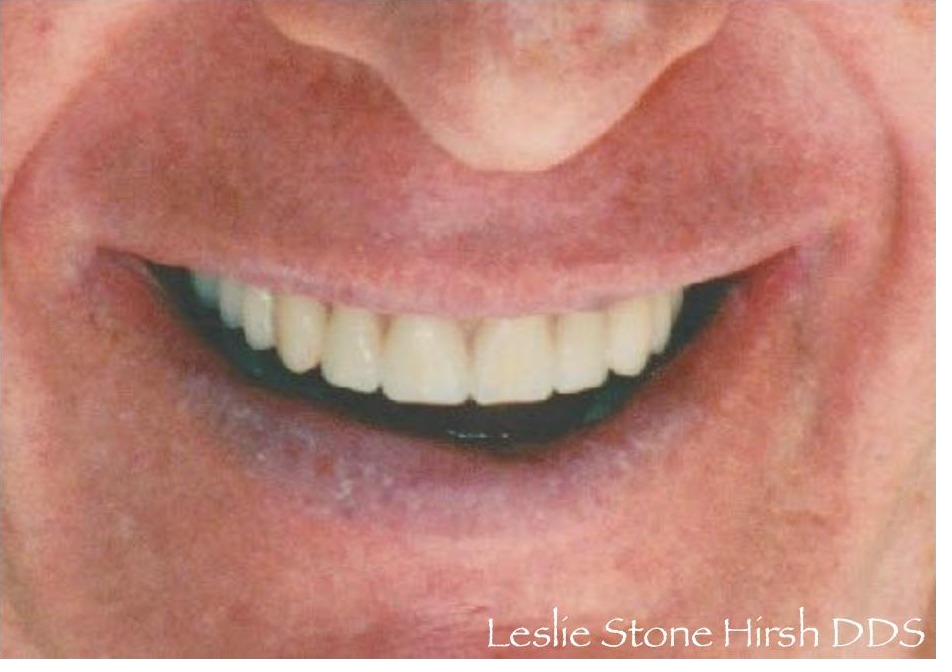

Following orthodontic treatment and periodontal crown lengthening, I fabricated 8 upper veneers for this patient. She was thrilled with her smile and the result of our interdisciplinary care.

This patient wanted a more attractive smile. Following orthodontic treatment and esthetic crown lengthening, I fabricated veneers for her upper 8 teeth. She was thrilled with the result of our interdisciplinary care and said "Oh my God, they look so good! They're gorgeous! It's so worth it!"